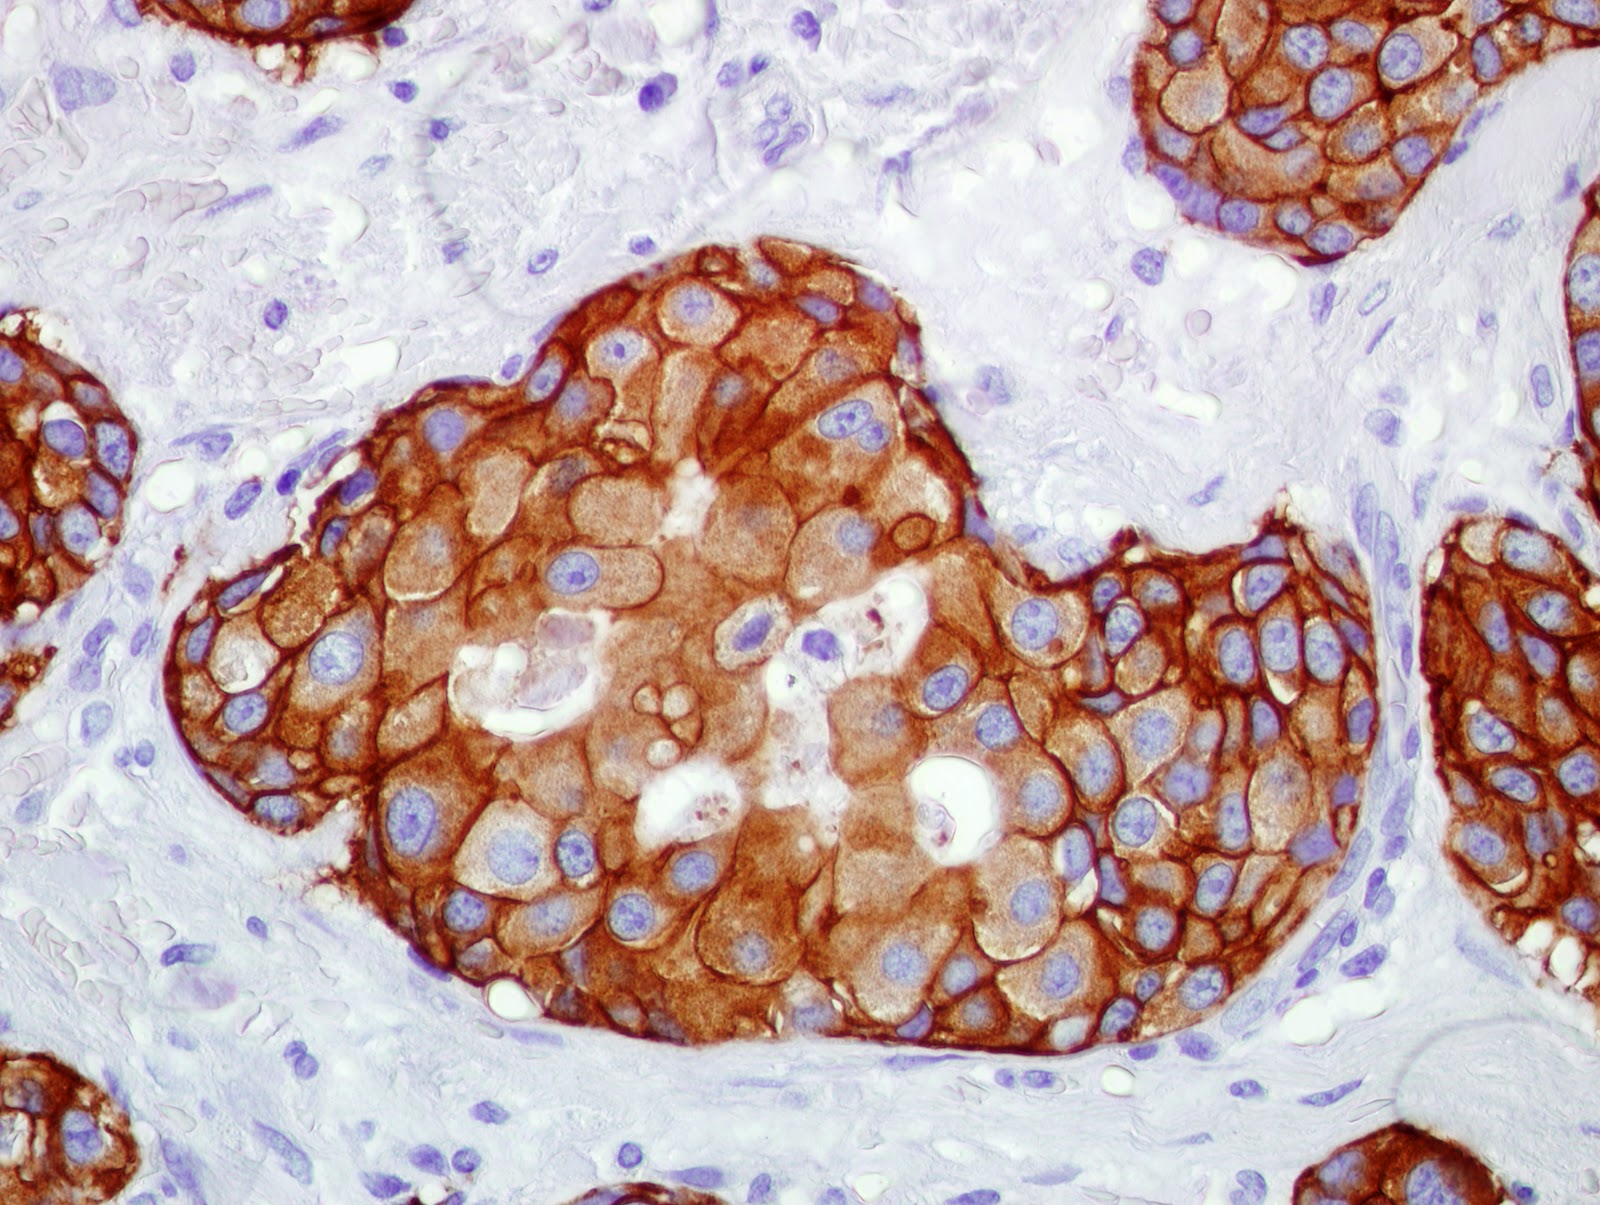

HER2/neupositive Breast Cancer pathology, diagnosis, cause, symptoms

From laboratoriodepatologiaortega.blogspot.com

LABORATORIO DE INMUNOHISTOQUÍMICA Que Es Her2 Positivo si los resultados de la prueba indican 3+, el cáncer es her2 positivo, por lo que la persona podría beneficiarse de. el her2 es una proteína que participa en el crecimiento celular y que puede estar amplificada en el cáncer de mama. Las pruebas de her2 ayudan a determinar el. el her2 (receptor 2 del factor de. Que Es Her2 Positivo.